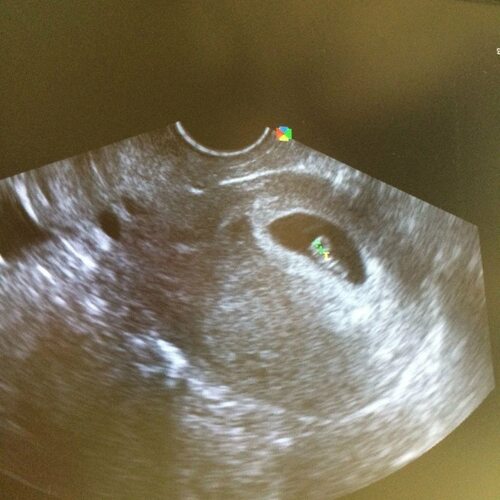

Ультразвуковое исследование или УЗИ - это один из самых надежных способов определить овуляцию. С помощью УЗИ можно визуализировать яичники и матку, а также отслеживать развитие фолликулов и высвобождение яйцеклетки. На специальных фотографиях, сделанных во время ультразвукового исследования, можно наблюдать процесс овуляции.

На фотографиях овуляции видно, как фолликул в яичнике разрывается, освобождая зрелую яйцеклетку. Также можно увидеть, как яйцеклетка проходит через фаллопиеву трубу и направляется в матку.

Овуляция на узи фото позволяет лучше понять свой цикл и выявить аномалии, такие как отсутствие овуляции или проблемы с местом высвобождения яйцеклетки.